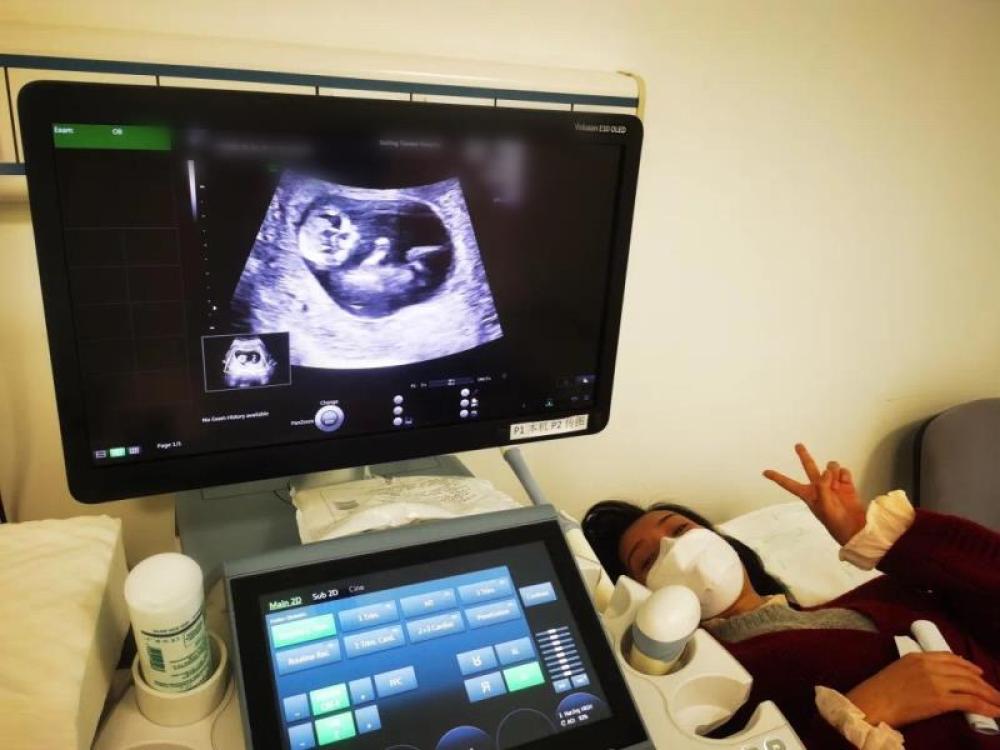

今天是我來武漢的第54天,第一次通過B超影像見到了“小家伙”。

今天一早,妻子去醫(yī)院進行B超檢查,同事用手機拍攝下了B超顯示屏上的畫面,記錄下了這個87天的小家伙第一次“亮相”。

圖為北京天壇醫(yī)院袁磊愛人做B超檢查。

“袁磊,看看你們家寶寶,可愛嗎?”收到同事發(fā)來的視頻,第一眼就看哭了,身邊的同事看完視頻也哭了。

視頻里,這個小家伙好像聽到了外面的召喚,在媽媽的肚子里伸手、踢腿、翻身,用各種動作進行回應……看到他那小胳膊小腿,一種從未有過的幸福感不停地向上涌,眼淚怎么也控制不住。

其實在武漢這么多天,他一直就是我的牽掛,今天終于看到他了,那種感受真是又緊張又激動,雖然還看不清他的樣子,但是已經感受到他的活力。